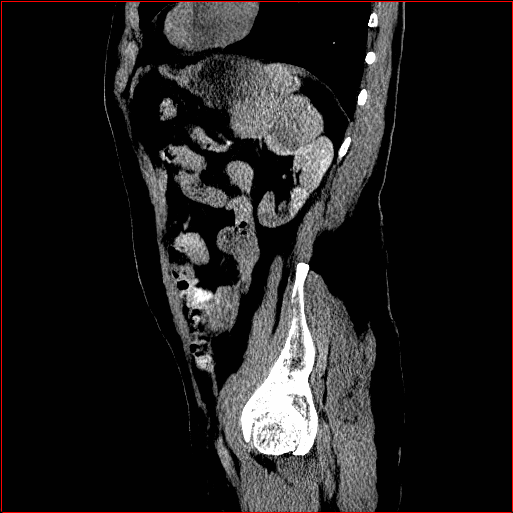

Liver Tumor

0.75×0.75×0.50.75\times 0.75\times 0.5

mm

512×512×768512\times 512\times 768

Figure 5: MAISI-v2 segmentation-guided results for five types of tumors. We show results for different voxel spacing and volume size to demonstrate the flexibility of MAISI-v2. Different Hounsfield Unit window is used to better show the contrast between tumor and normal tissues.